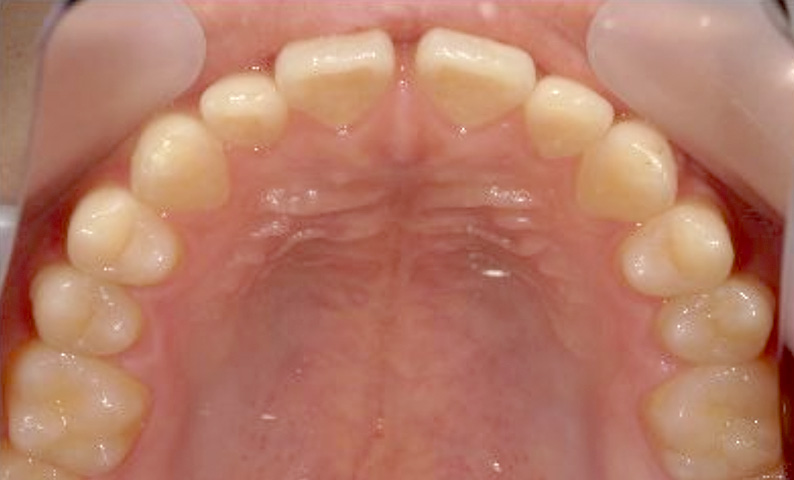

症例_024 上顎だけの部分矯正

治療期間:7ヶ月金額:30万円+税女性前歯のガタガタ上の前歯だけ

| Before | After |